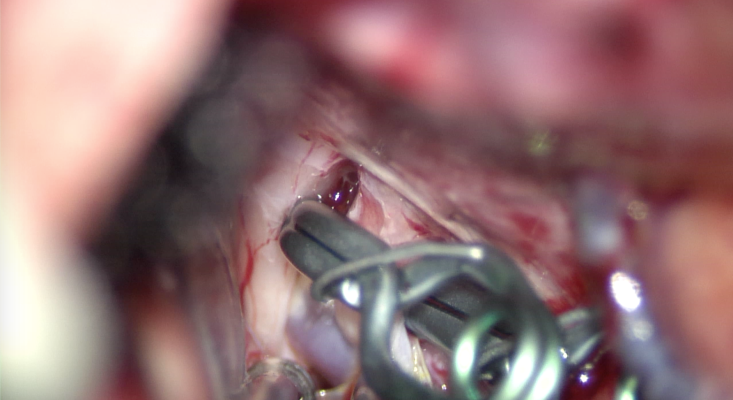

- Clipagem microcirúrgica – nesta modalidade é colocado um clipe por fora do aneurisma